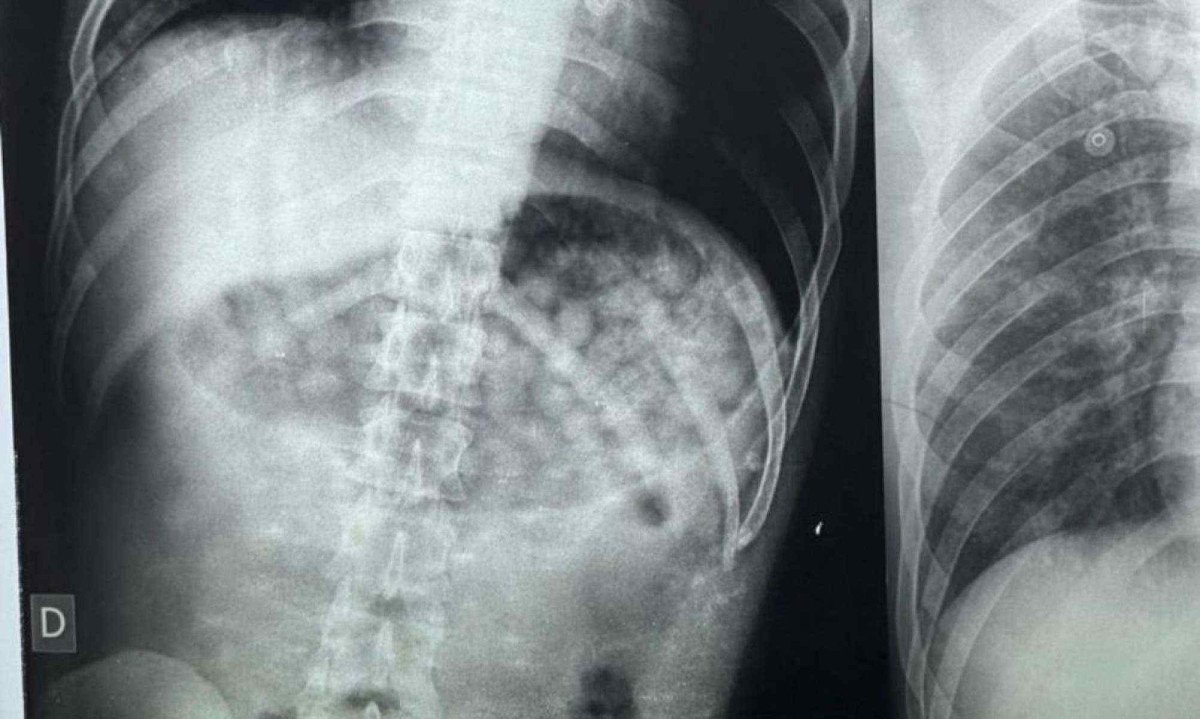

Após receber os primeiros socorros e dar entrada no hospital, foi feito um exame de raio-x que registrou uma grande quantidade de droga no corpo do homem. Segundo a equipe médica, só seria possível determinar a quantidade exata após evacuação ou cirurgia. Momentos depois, ele vomitou mais 61 embalagens com a mesma substância.

Ao todo, 61 embalagens de substância similar a maconha foram expelidas pelo homem

Ao todo, 61 embalagens de substância similar a maconha foram expelidas pelo homem Divulgação/Polícia Militar